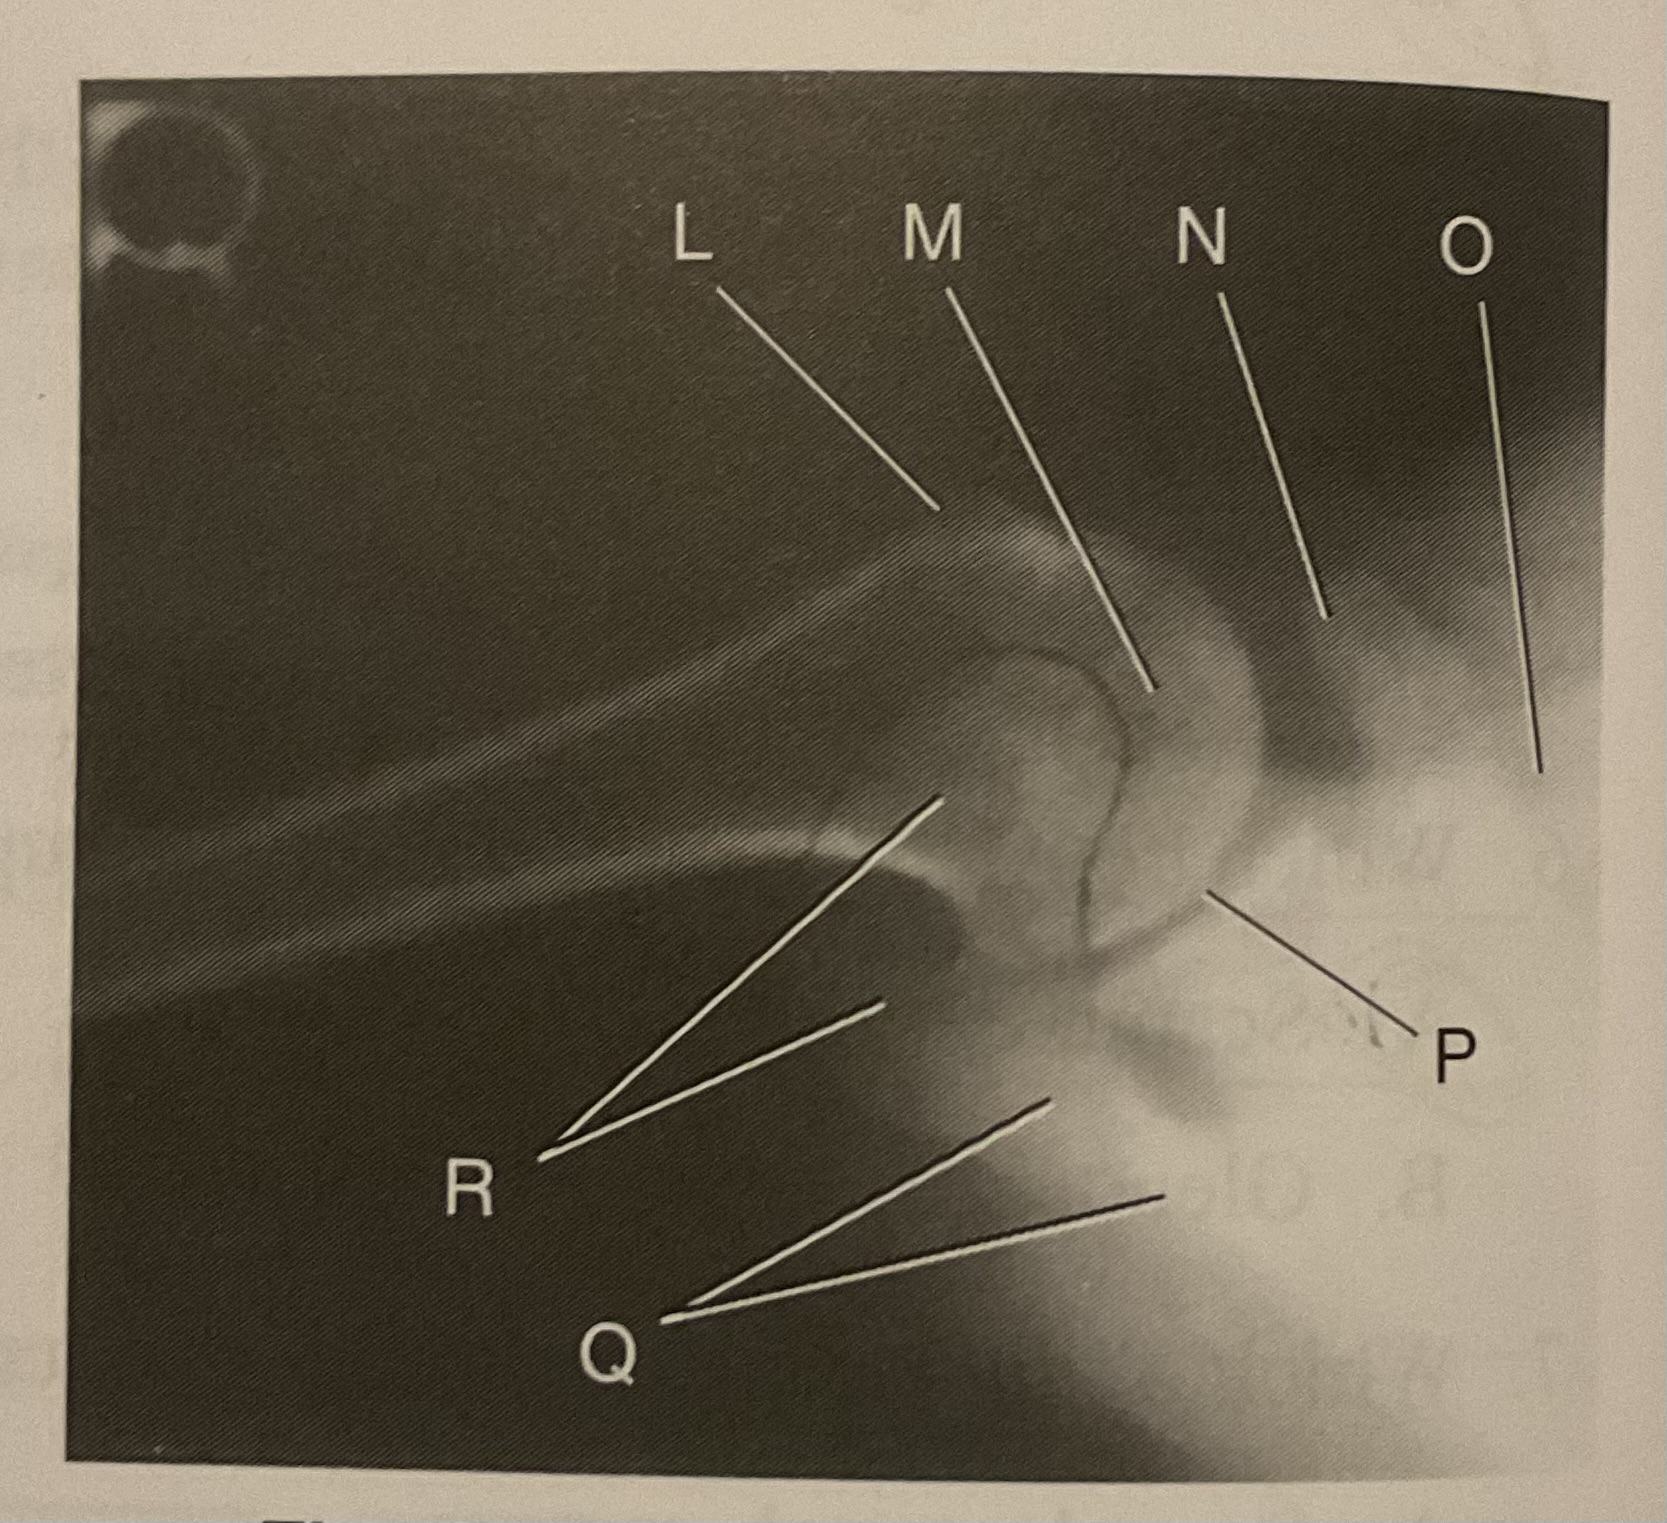

What AP projection does this image represent?

External

L?

Lesser tubercle

M?

Head of humerus

N?

Coracoid process

O?

Clavicle or lateral extremity of clavicle

P?

Glenoid cavity or Scapulohumeral joint

Q?

Spine of scapula

R?

Acromion of scapula

What is the correct term and method for the projection seen in this image?

Inferosuperior axial projection